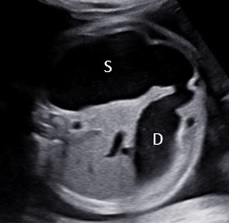

ắc tá tràng bẩm sinh (Congenital Duodenal Obstruction – CDO) là hậu quả của những sai sót trong quá trình phát triển phôi thai học